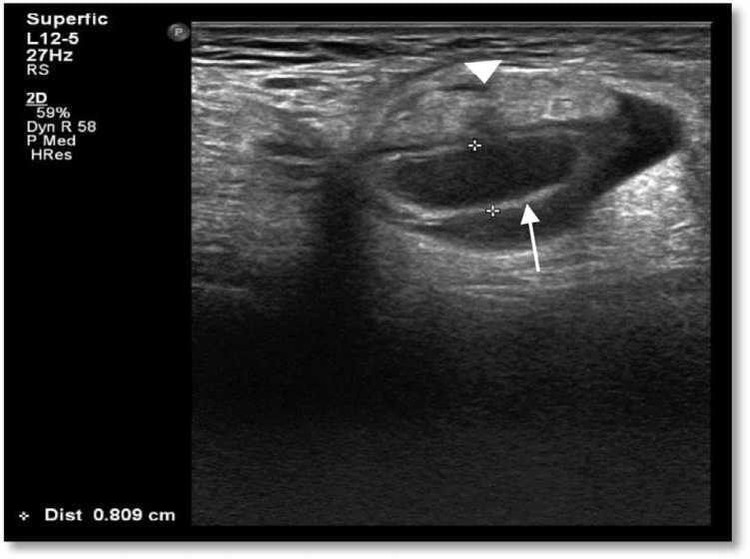

Chụp CT bụng có tiêm thuốc cản quang cho thấy ruột thừa phù nề thoát vị với các sợi mỡ liền kề. Túi thoát vị có kích thước 5,2 x 3,4 x 5cm.

thoat-vi-dui-chua-ruot-thua-1.jpg

Hình 2